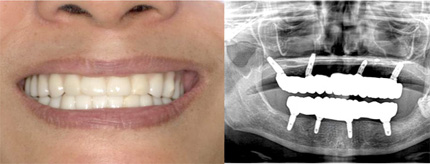

ボロボロの歯の状態を1回目の治療で、歯の痛みや腫れだけでなく、歯の大きさ、色、形、歯並びまでをすべてきれいにし、最短2回で自然な状態にする”カスタムセラミック法”という治療です。

セラミックを被せて治療完了 仮歯を外し、セラミックの歯を被せて、自分の歯のような自然なきれいな状態になります。 |

オールオン4の治療例:1

オールオン4の治療例:2